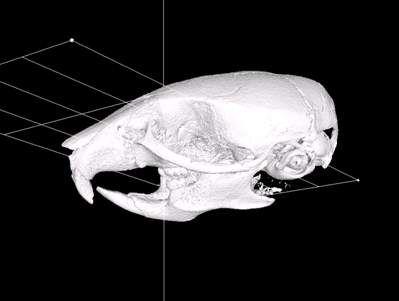

Building generic anatomical models using virtual model cutting and iterative registration

Using 3D generic models to statistically analyze trends in biological structure changes is an important tool in morphometrics research. In this article we show how the creation of a generic model that captures spatial information exploitable in statistical analyses is facilitated by coupling our generalized segmentation method to existing automatic image registration algorithms.

(open access article @ BMC-MI, reference).

Fast Interactive Integration of Cross-sectional Image Datasets and Surface Data for Morphometric Analysis

A system to align a stack of images in parallel for the reconstruction of a 3D data structure and surface model from a set of histological cross-sections is presented, along with complementary tools for interactive alignment. introduced.

(journal article, online article @ SHTI, poster @ iCore, reference).

An Efficient Virtual Dissection Tool to Create Generic Models for Anatomical Atlases

A method is presented to combine 3D mesh cutting tools to extract a particular object from a polygonal mesh of amalgamated structures. With this technique it is possible to extract individual objects, such as the jawbone from a skull, from a polygonal model.

(journal article, online article @ SHTI, reference).